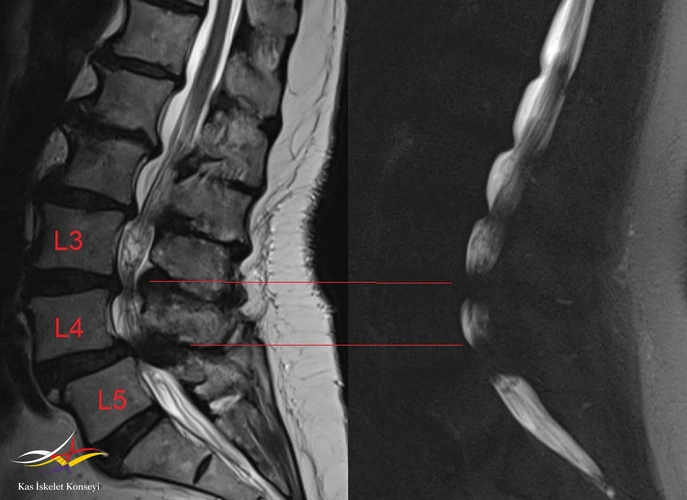

Resim 2. Lomber BT incelemesi.

Resim 6. Sagitaal MRG ve MRG myelografide darlık seviyeleri.